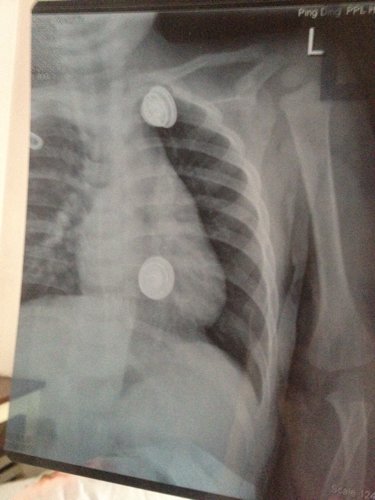

一岁半宝宝从写字台上掉下'诊断结果为左锁骨中段青枝骨折。请问'愈合需要多长时间'需注意什么。会不会留下什么后遗症。饮食上需要补吗?

病情分析: 您好,这个是一个轻微的骨折,这个愈合很快的,一般来说1到3月就可以完全愈合的 指导意见: 小孩的再生能力强,愈合比成年人快,但是要注意适当的制动